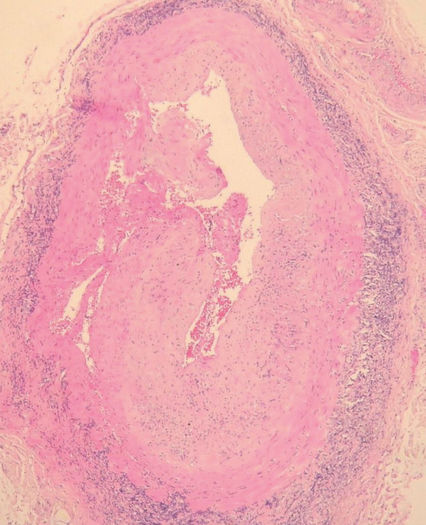

3. Granulomatosis de Wegener

1. Triada

1. Granulomas

1. Vasculitis necrotizante

1. Nefropatía

2. Daño

1. Vasos sanguíneos

1. Vías respitarotrias

2. Anticuerpos

1. C-ANCA